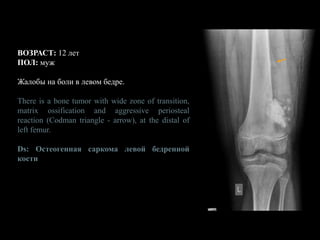

ВОЗРАСТ: 12 лет

ПОЛ: муж

Жалобы на боли в левом бедре.

There is a bone tumor with wide zone of transition,

matrix ossification and aggressive periosteal

reaction (Codman triangle - arrow), at the distal of

left femur.

Ds: Остеогенная саркома левой бедренной

кости